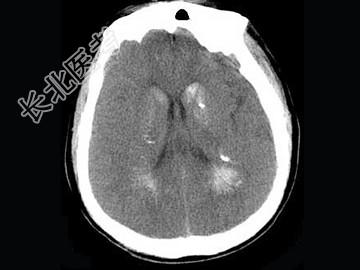

- 单项选择题男,52岁, 无明显不适,CT检查, 最可能的诊断为 ( )

A、脑血管畸形

B、结节性硬化

C、甲状旁腺功能低下

D、脑颜面血管瘤病

E、转移瘤